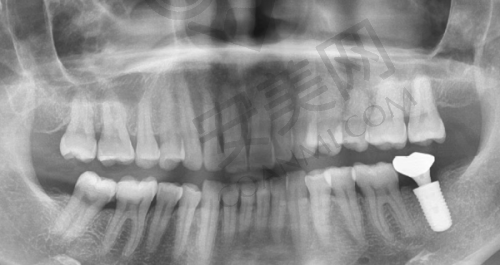

首先,患者需要到乌鲁木齐美奥口腔进行全方面的口腔检查,包括口腔CT扫描等,以确定患者的口腔状况和种植方案。然后,王旭医生会与患者进行详细的沟通,解释种植方案的具体内容和注意事项,患者可以根据自己的情况进行选择和调整。接下来就是种植手术阶段,在局部麻醉下,王旭医生会将韩国登腾种植体植入患者的牙槽骨内。手术后,患者需要按照医生的嘱咐进行休息和护理,等待种植体与牙槽骨愈合。一般需要几个月的时间,待种植体稳定后,再安装全瓷冠。末尾,医生会对患者进行复查,确保种植成效达到预期。